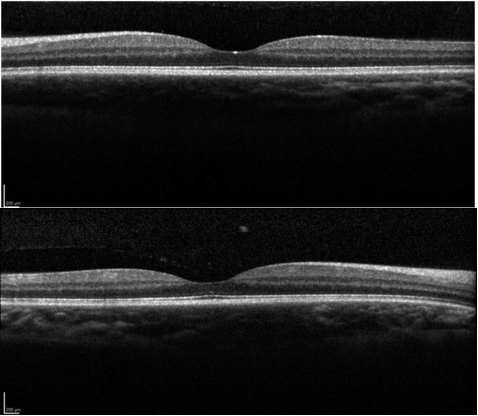

右眼 8 点钟位置可见一处羽毛状边缘的黑色素沉着病变,左眼 3 点钟方向也可见一直径较小的黑色素沉着病变(图 1)。眼底 OCT 发现双眼明显的脉络膜增厚,视网膜层无明显异常(图 2)。

图 2 为眼底 OCT 图像:双眼脉络膜增厚,视网膜层正常